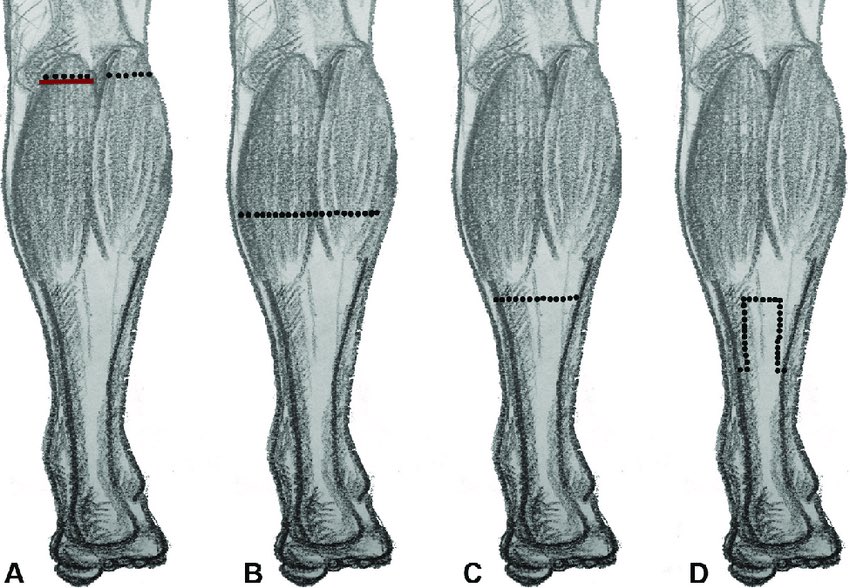

Pero si el motivo de la fascitis es una contractura del tríceps sural (es decir, si el test de Silfverskiöld es positivo), podemos hacer una alargamiento de gastrocnemios. Se puede hacer a muchos niveles, yo personalmente las hago a nivel proximal medial.